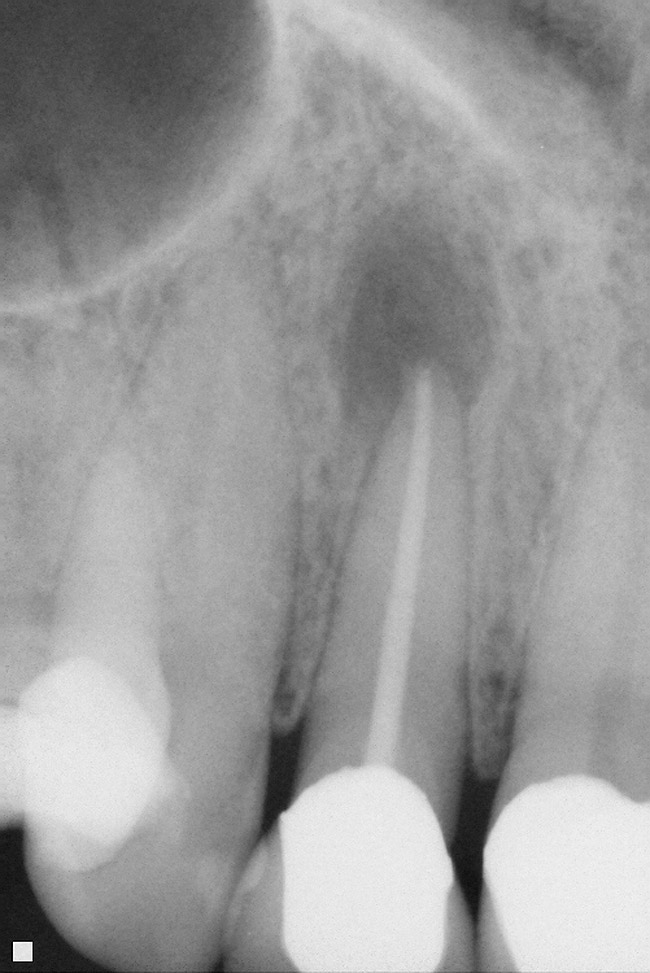

The decision to retain or extract a questionable tooth is one that occurs frequently in dental practice. There are many factors to consider when making this decision. Some situations are very straightforward (Figure 1) while others fall into a “gray” area of decision-making (Figure 2). This article will provide guidelines for determining whether to extract or retain a tooth when the decision is not so straightforward using structural, periodontal, endodontic, and esthetic criteria. Some teeth may involve only one of these areas, and some will involve various combinations of these areas. There are also other important factors to consider such as patient expectations, patient finances, and patient compliance, but these topics vary from patient to patient and should be discussed with each individual patient. While these topics are very important to the decision-making process, they are beyond the scope of this article.